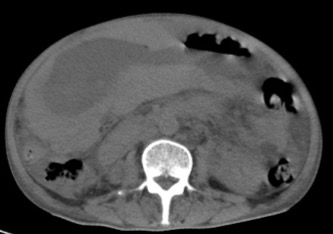

Gastric abnormalities show nonspecific gastrointestinal symptoms and similarly radiological findings. Intra and extra luminal gastric wall thickening are the most common finding in benign and malignant pathologic process. This aim of this case report was to describe several characteristics such as the location and size of the lesion, involvement of the gastric wall and surrounding structures, calcifications, and contrast enhancement pattern which can assist in radiological diagnosis. Several cases at our institution have similar gastrointestinal complaints, however, there were different lesions characteristic found in contrast enhanced abdominal CT scan. The first case 72-years-old man experienced hematemesis with radiologic finding diffuse gastric mucosal thickening as well as homogenous contrast enhancement but without calcification. The second case 37-years-old man complaint dizziness and melena with radiologic finding large tumor more than 10 cm in size, amorph calcification and heterogenous contrast enhancement. The last 60-years-old man case experienced melena and hematemesis, from abdominal CT scan showed irregular gastric mucosal thickening with heterogenous contrast enhancement and fat stranding around the lesion, without calcification. Methods used in these cases were contrast-enhanced abdominal CT scan, esophagogastroduodenoscopy (EGD), and biopsy in order to determine the diagnosis. Contrast-enhanced abdominal CT scan plays a vital role in describing the lesion characteristics which affects the determination of treatment options and future prognosis.